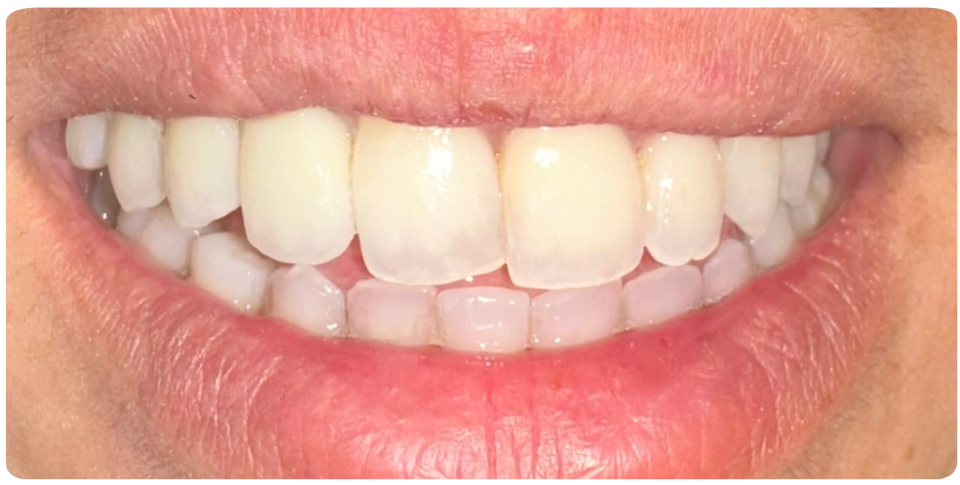

- Enhanced Function & Aesthetics – Restores chewing ability and a natural-looking smile.

Ideal for multiple missing teeth, implant-supported bridges offer a long-lasting and comfortable solution for restoring your smile.